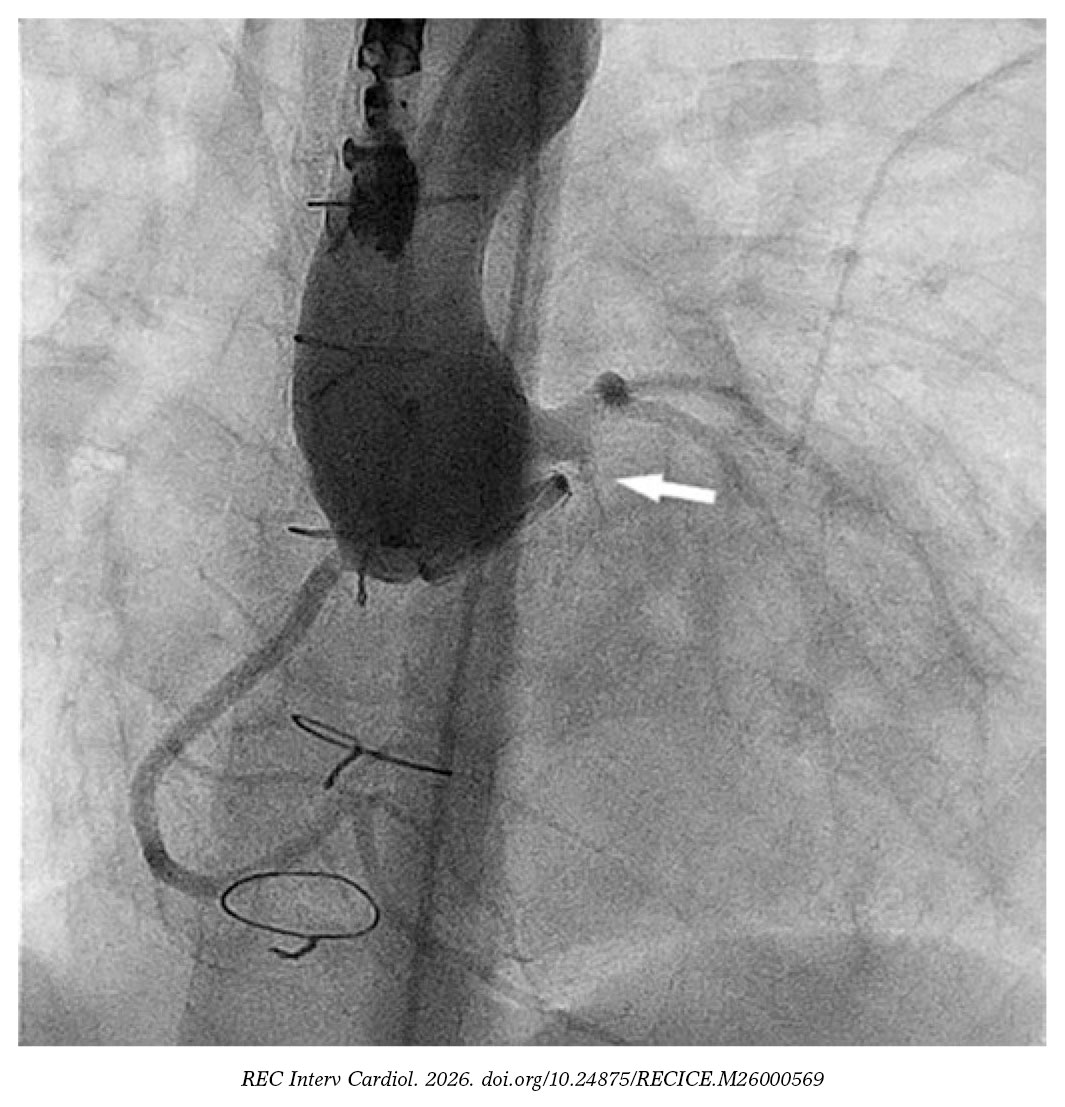

We catheterized the fistulous tract using a modified 4-Fr NIH catheter (Cordis, United States) and a 0.035 in hydrophilic guidewire. Afterwards, we mounted a 4-Fr delivery catheter over the guidewire, and deployed a 4 mm × 4-mm Nit-Occlud PDA device (PFM Medical, Germany) (figure 2 and video S2). We chose this device over nitinol mesh occluders because their greater length and retention discs were considered at risk of interfering with the coronary artery.

Figure 2.